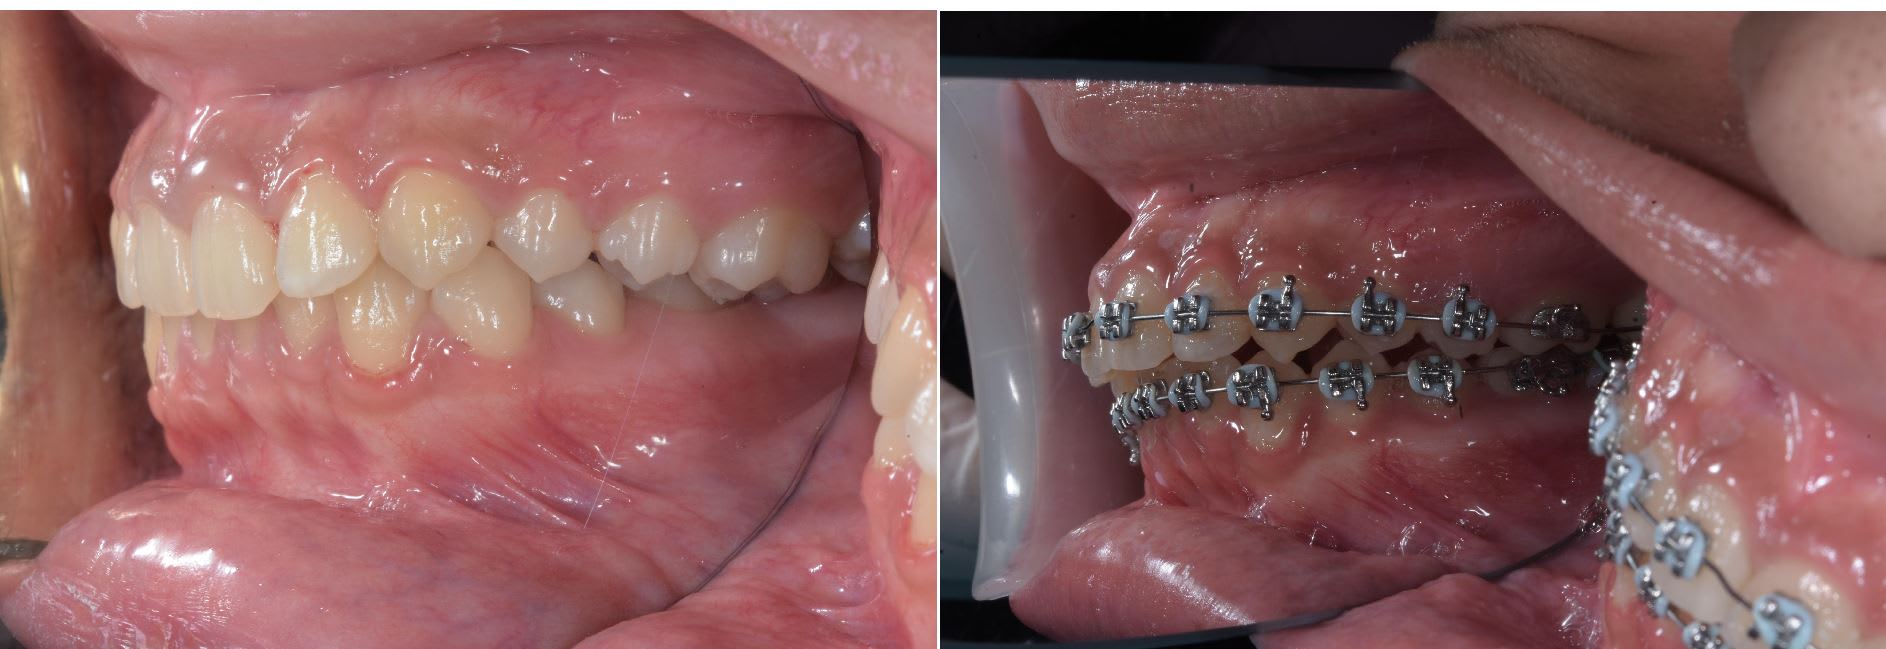

Un cas plus inhabituel Patient class III avec cross bite antérieur. Ici gros espaces en antérieur à la mandible. Vue le coté inhabituel j'ai fait un set up qui m'a indiqué qu'il fallait à la fois mésialer les secteurs postérieur supérieur et inférieure. Traduction pas de mécanique class III classique.

J'ai choisie les minivisse palatine car j'ai eu de bon résultat pour mesialé avec ce type de configuration , mais je cherche encore un système prédictible à la mandibule.

- comparé l'inclinaison post et durant traitement des incisives il y a eu compensation mais pas de changement majeurs

- le profile est amélioré

- la fonction ok

La langue à tout l'espace qui l'ui faut vue que je distalize la dentition maxillaire

Et je n'ai jamais dis que je ne voulais pas compenser les incisives inf , j'ai dit qu'il fallait mesialer les secteur post mandibulaire. et qu'une méchanique classique , power chaine + class III elastique ça risquer de ne pas passer.

Quelque photo avant après. Les pano sont intéressante car elles montre bien que l'on à mesialé l'ensemble des secteurs post, que sa soit à la mandibule ou au maxillaire.